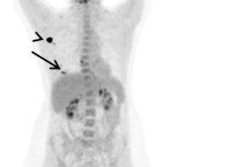

The researchers observed strong tracer accumulation in all 18 untreated primary breast malignancies. Clear tumor delineation was seen across different gradings, receptors, and histologic types, with a mean maximum SUV of 13.9 (range, 7.9 to 29.9) and a median lesion diameter of 26 mm (range, 9 to 155 mm). Separate studies have determined mean SUVmax uptake of FDG in primary breast cancer tumors is 5.7.

In addition, all preoperatively verified lymph node metastases in 13 women showed strong tracer accumulation (mean SUVmax = 12.2). Tracer uptake established or supported extra-axillary lymph node involvement in seven women and affected therapy decisions in three women, the researchers reported.

Fibroblast-activation protein inhibitor breast PET/MRI scans. Oblique coronal projections of prone breast PET/MRI maximum intensity projection images in all 18 patients who underwent breast PET/MRI. Image intensities are adjusted to standardized uptake value on a scale of 0-10. Image courtesy of Radiology.In an accompanying editorial, Drs. David Mankoff, PhD, and Mark Sellmyer, PhD, of the University of Pennsylvania, rued the researchers' choice of PET/MRI versus the more widely used PET/CT. MRI may hold advantages for imaging primary tumors, yet studies comparing PET/MRI and PET/CT for breast cancer nodal and distant disease staging are limited. In these settings, no studies to date show major advantages of PET/MRI over PET/CT, they stated.